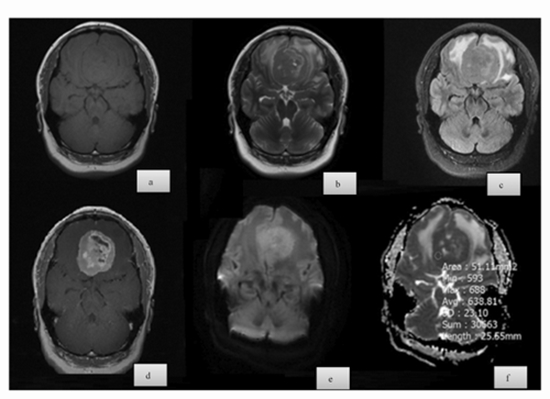

Is There Any Correlation Between Diffusion-Weighted Imaging and Histopathologic Findings of Meningioma? A Retrospective Study

Background and aims: Meningiomas are common CNS tumors, with grading critical for treatment. This study aimed to determine if diffusion-weighted imaging (DWI) correlates with histopathologic findings in meningioma, focusing on tumor grade, subtype, and Ki-67 index.

Methods: This retrospective study included 68 patients with meningioma who underwent preoperative MRI with DWI. Tumor grade was determined using the WHO classification. DWI intensity was categorized as hyperintense, isointense, or hypointense relative to normal brain tissue. ADC values were measured, and diffusion restriction was defined as high signal intensity on DWI with low signal intensity on the ADC map. Histopathologic analysis assessed the Ki-67 proliferation index. Statistical analysis used ANOVA, Chi-square, univariable linear regression (β), and odds ratios (OR) via SPSS 17.0, with p < 0.05 as significant.

Results: The study included 68 patients with a mean age of 52.1 ± 15.6 years, mostly females (67.65%). Most tumors were grade 1 (73.5%) with male patients having higher tumor grades than females. Meningothelial was the most common subtype. DWI intensity correlated with tumor grade, with higher grades more likely to be hypointense. ADC values varied with tumor grades, being significantly higher in grade 1 tumors. Diffusion restriction was more common in higher-grade tumors. Ki-67 was higher in males (p = 0.01) and inversely linked to ADC (p < 0.001).

Conclusion: Both qualitative DWI features and quantitative ADC values reflect meningioma grade and proliferative activity, with notable sex and subtype differences, underscoring the clinical utility of preoperative DWI.